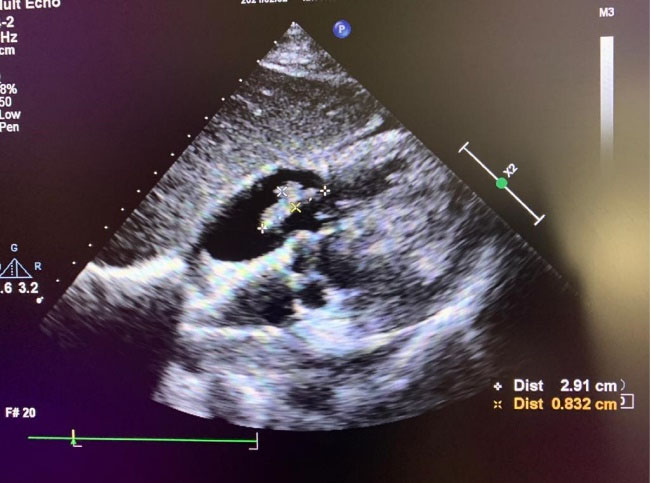

The results of initial laboratory tests showed leukocytosis (White Blood Cells: 18000 per microliter) with 82% neutrophils, Erythrocyte Sedimentation Rate (ESR):42mm/hour and C-Reactive Protein (CRP) was elevated. The blood cultures were also taken from two different sites and were negative. COVID-19 PCR test was done and was negative. Electrocardiogram (ECG) revealed sinus tachycardia, left axis deviation and evidence of Left Ventricular Hypertrophy (LVH). In echocardiography, left ventricular Ejection Fraction was normal with mild LVH with no wall motion abnormality. But a large (2.9 *0.8cm) mobile heterogeneous echo density was seen on atrial side of Tricuspid Valve (TV) that resulted in destruction of TV with severe Tricuspid Regurgitation (TR) in favor of vegetation. (Figure 2, Supplementary File, Video 4).

Figure 2.

subcostal view of transthoracic echocardiography that showed large(2.9*0.8cm) mobile mass on atrial side of tricuspid valve, suggestive of vegetation